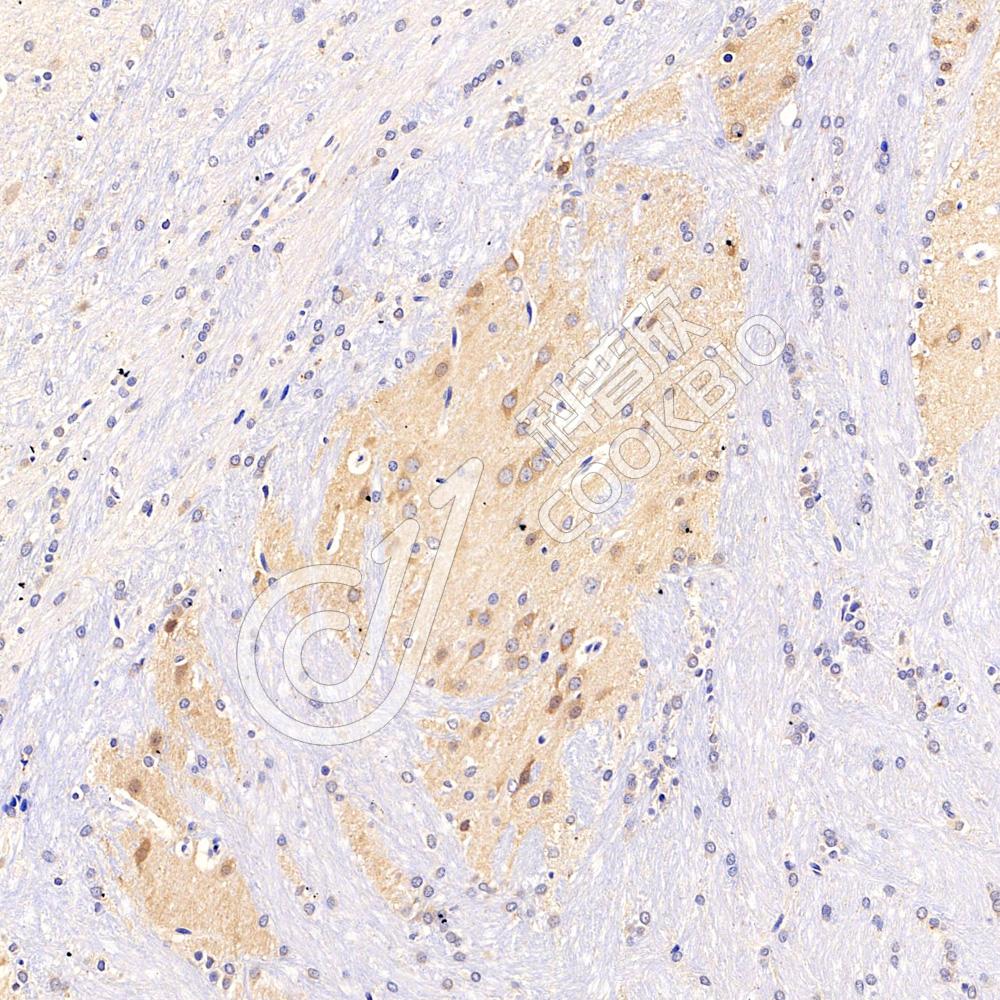

IHC检测RASGRP3蛋白(货号 K135802).

样品: 小鼠脑, 4%多聚甲醛 (货号KSG1101) 固定12-24小时.

抗原修复: 柠檬酸抗原修复液(干粉, pH 6.0) (KSG1201), 98℃, 20分钟.

—抗: 1: 600稀释, 4℃ 孵育过夜.

二抗: S-vision免疫组化多聚二抗(山羊抗兔),即用型 (货号KB3906), 室温孵育20分钟.

样品: 大鼠脑, 4%多聚甲醛 (货号KSG1101) 固定12-24小时.